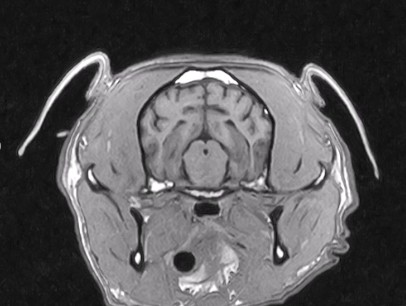

W obrębie mózgowia i trzewioczaszki najczęstszymi wskazaniami do badania MRI są:

• proces nowotworowy

• wodogłowie

• ziarniakowe zapaleniu mózgu i opon mózgowych

• diagnostyka zmian udarowych

• wstępna diagnostyka tętniaków i malformacji naczyniowych

• wstępna diagnoza gruczołu przysadki